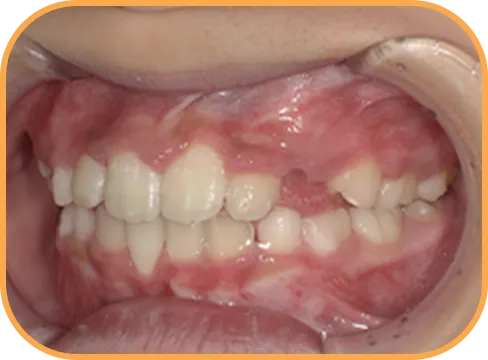

• After

• 右 側

治療後右側からの歯の様子

主 訴

前歯がでている、噛み合わせが深い

治療内容

インビザライン・ファースト

治療期間

10か月

治療費(税別)

450,000円+診断料30,000円

リスク・副作用

• 親知らずの影響や加齢などによって、凸凹が生じる可能性があります。

• 治療の初期段階では痛みや不快感が生じやすくなりますが、1週間前後で慣れます。

• 顎の成長発育によって、噛み合わせや歯並びが変化する可能性があります。

• 状況により当初予定した治療計画を変更する可能性があります。